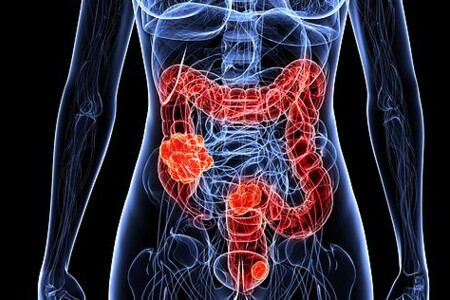

Tlusté střevo je koncovou částí trávicí trubice. Navazuje na tenké střevo a končí konečníkem. Tlusté střevo slouží ke vstřebávání především vody a tím dochází k zahušťování zbylé tráveniny a tvorbě stolice. Tlusté střevo však může být postiženo celou řadou nemocí, z nichž nejzávažnější je rakovina tlustého střeva, odborně kolorektální karcninom.

Nádory tlustého střeva jsou civilizační chorobou, která se objevuje čím dál častěji. Kolorektální karcinom je nejzávažnějším z nich, jde o zhoubný nádor tlustého střeva, který bez léčby metastazuje a přímo ohrožuje nemocného na životě. Prevence tohoto zhoubného nádoru tlustého střeva je přitom na vysoké úrovni.

Karcinom tlustého střeva je onemocnění, které má bohužel v České republice vysoký výskyt. I v celosvětovém měřítku je naše země jednou s nejvyšším výskytem. Onemocnění vzniká většinou ve vyšším věku, o něco častěji postihuje muže.